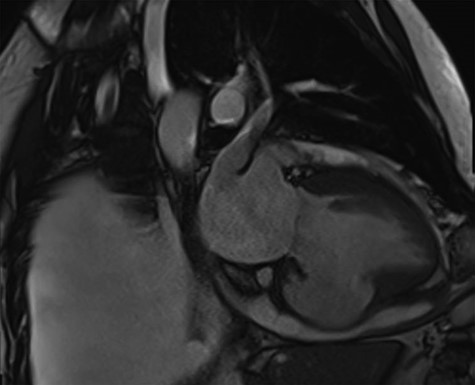

Cardiac MRI described a large aneurysm involving the basal and mid-inferoseptum and extending into the basal and mid-inferior walls (Fig. 2). There was full thickness infarction of the aneurysmal wall and an associated complex VSD with significant left to right flow (Qp:Qs 2.8:1). Coronary angiogram showed a mild circumflex disease and a significant disease of the left anterior descending (LAD) and right coronary artery (RCA) (Fig. 3).

Coronary angiogram demonstrating a diffuse coronary artery disease in the distribution of the left coronary artery.